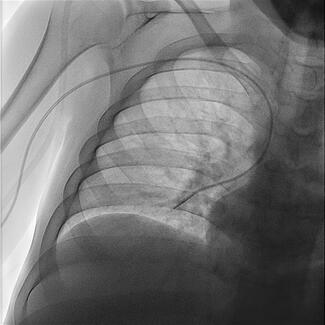

A 69-year-old obese man who had undergone permanent pacemaker implantation (VVIR, Medtronic) 3 weeks prior presented with a one-day history of experiencing continued, forceful pulsations in his abdomen followed by presyncope.